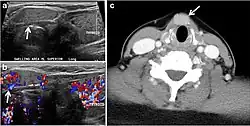

- Fig. 8. A 48-year-old male patient post total thyroidectomy with PTC recurrence. a Transverse greyscale ultrasound of the neck demonstrates a left thyroid bed heterogeneous, predominantly hypoechoic irregular lesion with calcifications (white arrow). b A spot image of iodine 123 total body scan of the neck demonstrate a focus of abnormal radiotracer uptake at the left thyroid bed (Black arrows) between the annotated markers. c Enhanced axial CT scan of the neck demonstrates an enhancing large left thyroid bed mass (white arrow) with no calcifications. The lesion exerts a mass effect on the oesophagus (black arrow) and is inseparable from the trachea.[1]

- Fig. 9. A 58-year-old male patient with persistence PTC at thyroid bed with hypervascular nodal metastasis. a–c Transverse greyscale and colour Doppler neck ultrasound demonstrate hypoehoic soft tissue in the left thyroid bed (white arrow in a). There are a heterogeneous enlarged lymph nodes at level 2 and 3 with markedly increased vascularity (white arrow in b and c). d–f Enhanced axial CT images of the neck demonstrate a 2.7 × 1.4 cm hypodense soft tissue lesion anterior to the left carotid sheath (white arrow). There are left-sided enhancing abnormal and enlarged lymph nodes at cervical level 2 and 3 (black arrows).[1]